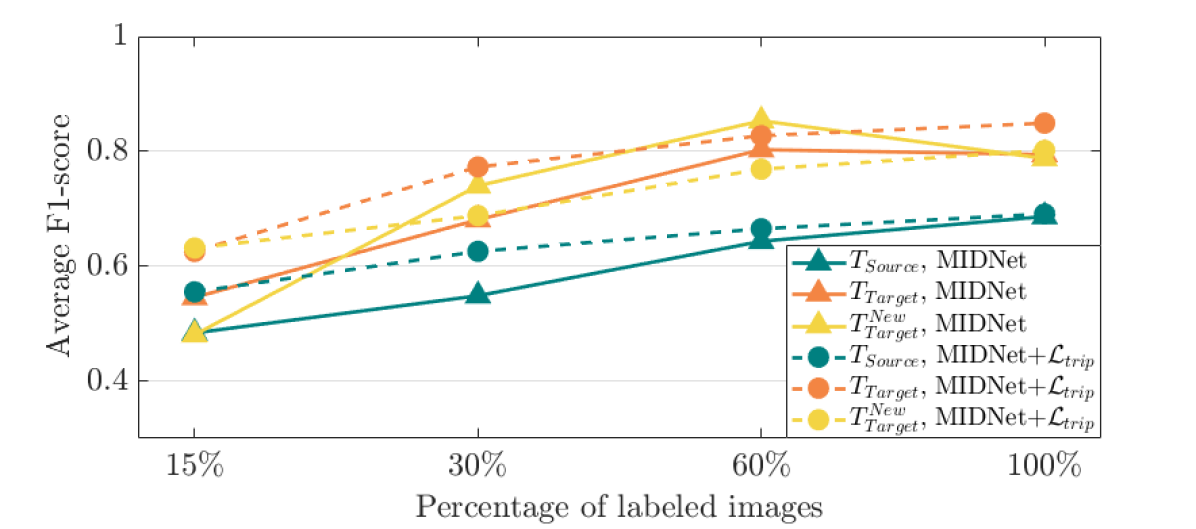

To explore the importance of labeled data, we evaluate the performance of MIDNet and MIDNet+ based on using and labeled data during training. Fig. 9 (a) shows the average F1-score on three groups of test data. From this figure, we observe that the classification performance improves with increasing labeled data.

From Fig. 9 (b), we observe that classification performance improves with the increase of labeled data in most cases. However, the performance reaches its peak after a certain percentage of labeled data is added. For example, the peak point is in this experiment.

To explore the importance of labeled data, we evaluate the performance of MIDNet based on using and labeled data during training. Fig. 15 shows the average F1-score of these experiments on three groups of test data. From this figure, we observe that the classification performance only slightly improves with increasing labeled data. This indicates that MIDNet is capable of achieving expected performance with sparsely labeled data. Additionally, excessive labeled data may lead to increased class imbalance. This may result in decreased classification performance as shown in Fig. 15 when the percentage of labeled training data increased from (i.e., all classes contain the same number of labeled images: 4294 images) to (i.e., Digit 1: 10768 labeled images vs. Digit 5: 4336 labeled images).